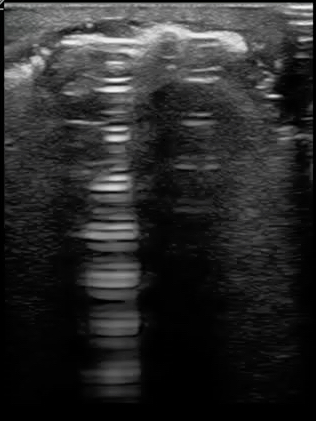

What if you are imaging an abscess or cellulitis and you identify something bright or hyperechoic you do not recognize? Air is a poor conductor of ultrasound waves and appears very hyperechoic and creates a “dirty shadow” deep to the air. This is not a very sensitive test for necrotizing fasciitis, but is specific. Every patient who I have identified subcutaneous air in has gone emergently to the operating room. Figure 11 demonstrates the hyperechoic appearance of air. A large collection of air may create a classic reverberation artifact as demonstrated in figure 12.

FIGURE 11. HYPERECHOIC AIR COLLECTING IN THE SUPERFICIAL PORTIONS OF A PATIENT’S SOFT TISSUE INFECTION. CONSISTENT WITH NECROTIZING FASCIITIS.

FIGURE 12. REVERBERATION ARTIFACT FROM A LARGE COLLECTION OF AIR IN A PATIENT’S SOFT TISSUE INFECTION. CONSISTENT WITH NECROTIZING FASCIITIS.